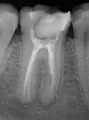

У меня была, в коренном зубе снизу - дырка без пломбы, пломба выпала - была временной. Вот так ходила несколько месяцев. В итоге: последнее время стал болеть зуб и я его, случайно, повредила твердой пищей, там и до нерва похоже дошло. И вот я сходила к врачу, она запломбировала зуб с лекарством и назначила лечение, через пятнадцать дней, примерно. Изначально зуб не болел и неприятных ощущений не было, но спустя сутки стал болеть, и со временем все сильнее. Сильное ощущение сдавленности в зубе со всех сторон, больно жевать и при слабом надавливании больно.

Нормально ли это? Вот уже третий день болит, стоит ли обратиться, раньше времени, к врачу?